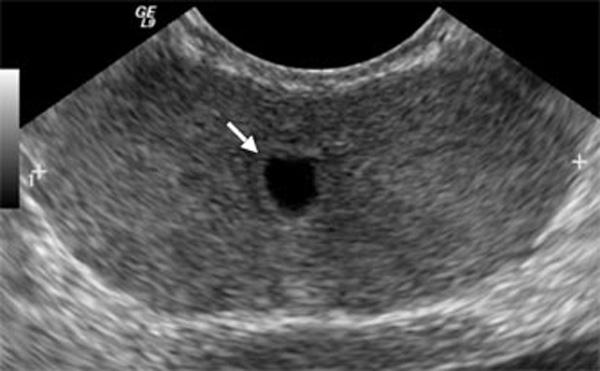

Urachal Cyst

Ureteroceles